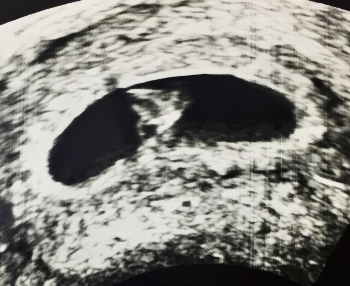

✅ 보통 6주 이후부터 심음이 확인되며, 6-12주 사이의 CRL 길이를 기준으로 임신주수를 정하게 됩니다.

✅ 머리 엉덩 길이 (Crown-Rump Length) : 임신 1분기 아기의 크기를 재는 기준이 됩니다.

아기집 (Gestational Sac, GS)으로도 주수를 추정할 수 있지만 CRL을 사용하는 경향이 있습니다.

✅ 임신 초기의 아기 크기는 CRL로 측정하게 된다.